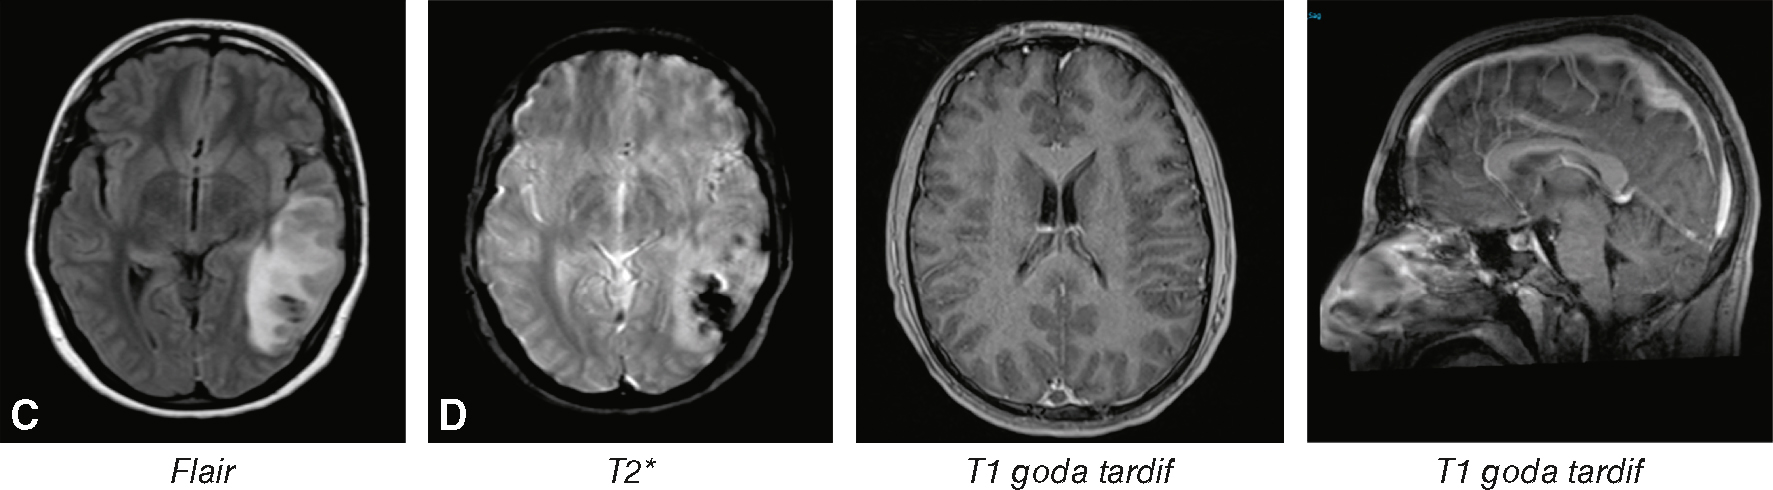

Quel(s) est (sont) votre (vos) diagnostic(s) devant cette IRM (fig. 33.1) ?

L'image montre quatre coupes d'IRM cérébrale, chacune utilisant une séquence différente pour visualiser différentes caractéristiques du cerveau. La première image, étiquetée "Flair", montre une coupe axiale du cerveau avec une séquence FLAIR (Fluid Attenuated Inversion Recovery), qui est utile pour détecter les lésions cérébrales, en particulier les zones de démyélinisation ou d'œdème. La deuxième image, étiquetée "T2", montre une coupe axiale avec une séquence T2 (T2 étoile), qui est sensible aux dépôts de fer et aux saignements, souvent utilisée pour détecter les microhémorragies. La troisième image, étiquetée "T1 gado tardif", montre une coupe axiale avec une séquence T1 après injection de gadolinium, un agent de contraste, qui aide à visualiser les zones de rupture de la barrière hémato-encéphalique, souvent associées à des tumeurs ou des inflammations. La quatrième image, également étiquetée "T1 gado tardif", montre une coupe sagittale du cerveau avec la même séquence T1 après injection de gadolinium, offrant une vue latérale pour une meilleure localisation des anomalies. Ces images sont intéressantes car elles montrent comment différentes séquences d'IRM peuvent être utilisées pour obtenir des informations complémentaires sur la structure et la pathologie du cerveau.

Réponse : A, B, C, D

Commentaire : il existe un signe du delta confirmant l’hypothèse de thrombose du sinus longitudinal supérieur.